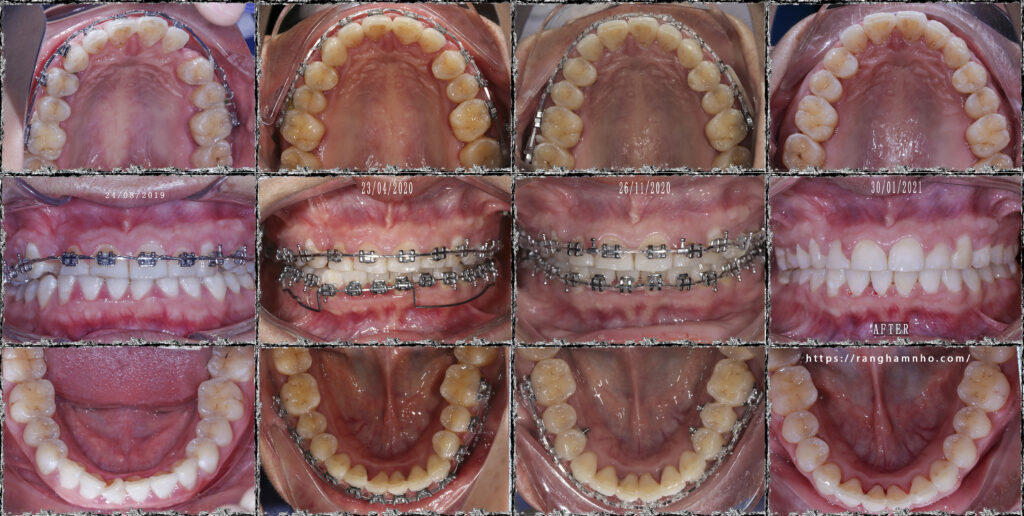

Trước điều trị: BN đã điều trị 2 năm tại 1 cơ sở nha khoa khác, và kết quả là, còn khoảng, răng còn xoay, khớp cắn chưa ổn định. R13 đáng phải giữ lại thì đã bị nhổ đi.

Phương án, ké di gần răng 4 về thay thế vị trí răng 3, xoay lại để làm đều nhóm răng cửa hàm dưới, bẻ torque để răng cửa trên đỡ chìa.

Kết quả: sau 1.5 năm điều trị, BN thoát niềng với các tiêu chỉ hoàn thành.